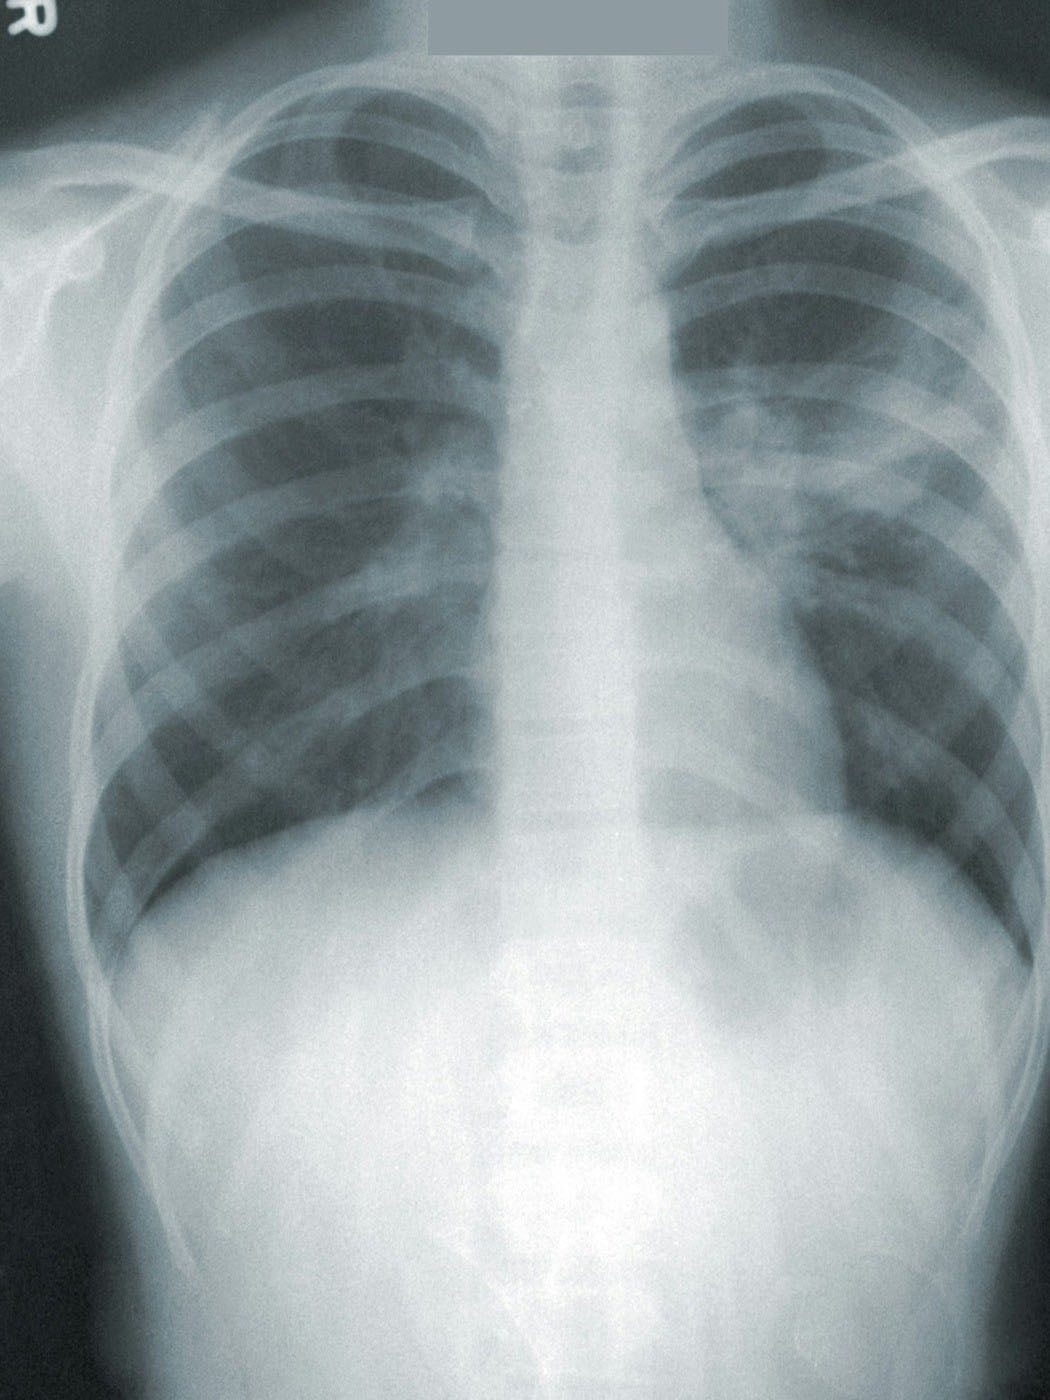

The Rio da Huila Medical Center's Imaging and Diagnostics department offers X-rays, ultrasounds, and other diagnostic services locally, making quality care affordable and accessible to rural patients. As a referral hospital for Rio da Huila Church, it not only provides medical treatment but also introduces many to the Christian faith in a supportive environment.